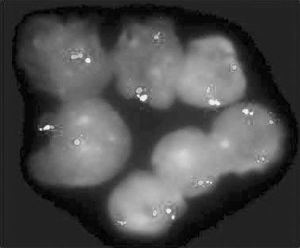

3.骨髓檢查 增生活躍,以粒系增生為主,原始粒細胞<10%,多為中晚幼粒細胞及桿狀核細胞粒∶紅為10~50∶1。部分患者可見骨髓纖維化。骨髓巨核細胞明顯增多,以成熟巨核細胞為主。骨髓培養集落與叢落皆增多